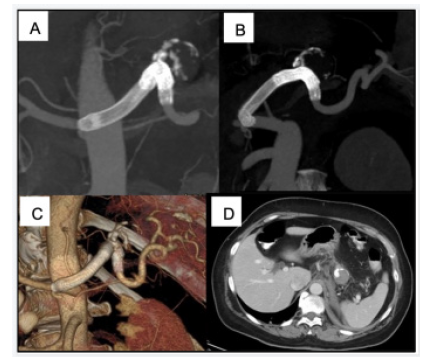

We present the case of a 57-year-old man who complained of upper left abdominal pain for 6 months. A CT angiography showed a 5 cm splenic artery aneurysm (Figure 1). His past medical history was not significant, and he had no significant comorbidities.

Figure 1: Preoperative CT angiography. MIP (A) and 3D reconstructions (B and C) show a 5 cm splenic artery aneurysm (arrows). The diameter of the splenic artery is 5 mm (D).